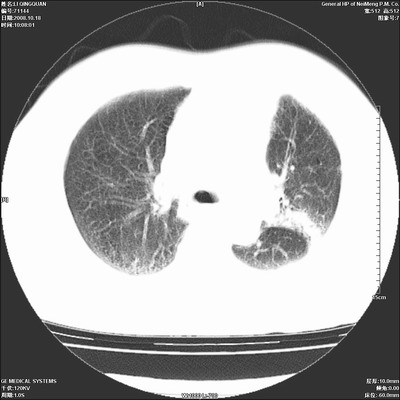

以下是引用ybing在2008-10-19 12:58:00的发言:[br]左肺上叶阻塞性炎症-建议支气管镜进一步检查除外中央型肺癌

以下是引用duguo在2008-10-19 13:59:00的发言:[br]左肺上叶支气管狭窄,首先考虑中心型肺癌伴阻塞性肺炎\\肺不张.

以下是引用随光逐影在2008-10-19 14:31:00的发言:[br]考虑左肺中央型肺癌并左肺上叶阻塞性肺炎,肺不张。